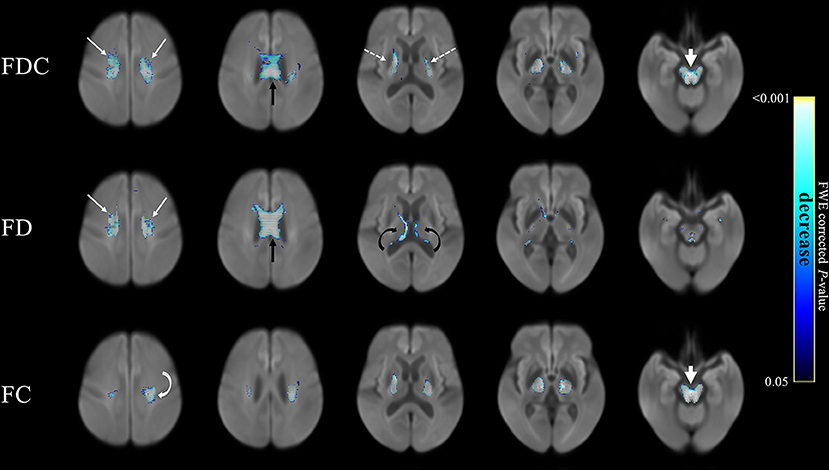

Here’s a graphical representation of the results. The features represented by the circles in each group interact with one another in a mutually reinforcing (the black bars) or interfering (the red bars) way. The thickness of the bars represents the strength of the interaction. An explanation in the researchers’ own words follows:

From Kumar et al. Mov Dis Clin Prac 2025

Network Analysis showing 16 signs/symptoms and their associations. Each node in figure represents symptom/sign, Black edges represent positive connection, and red edges represent negative connection; thicker edges represent stronger association.

V1, Sensitivity to bright light; V2, MoCA (Cognition Score); V3, Neck Rigidity; V4, Urinary Incontinence; V5, Emotional Incontinence; V6, Upward ocular movement dysfunction; V7, Downward ocular movement dysfunction; V8, Horizontal ocular movement dysfunction; V9, Eye lid dysfunction; V10, Limb apraxia; V11, FAB (Executive Score); V12, Gait dysfunction; V13, Bradykinesia; V14, Postural tremor; V15, Kinetic tremor; V16, Rest tremor.